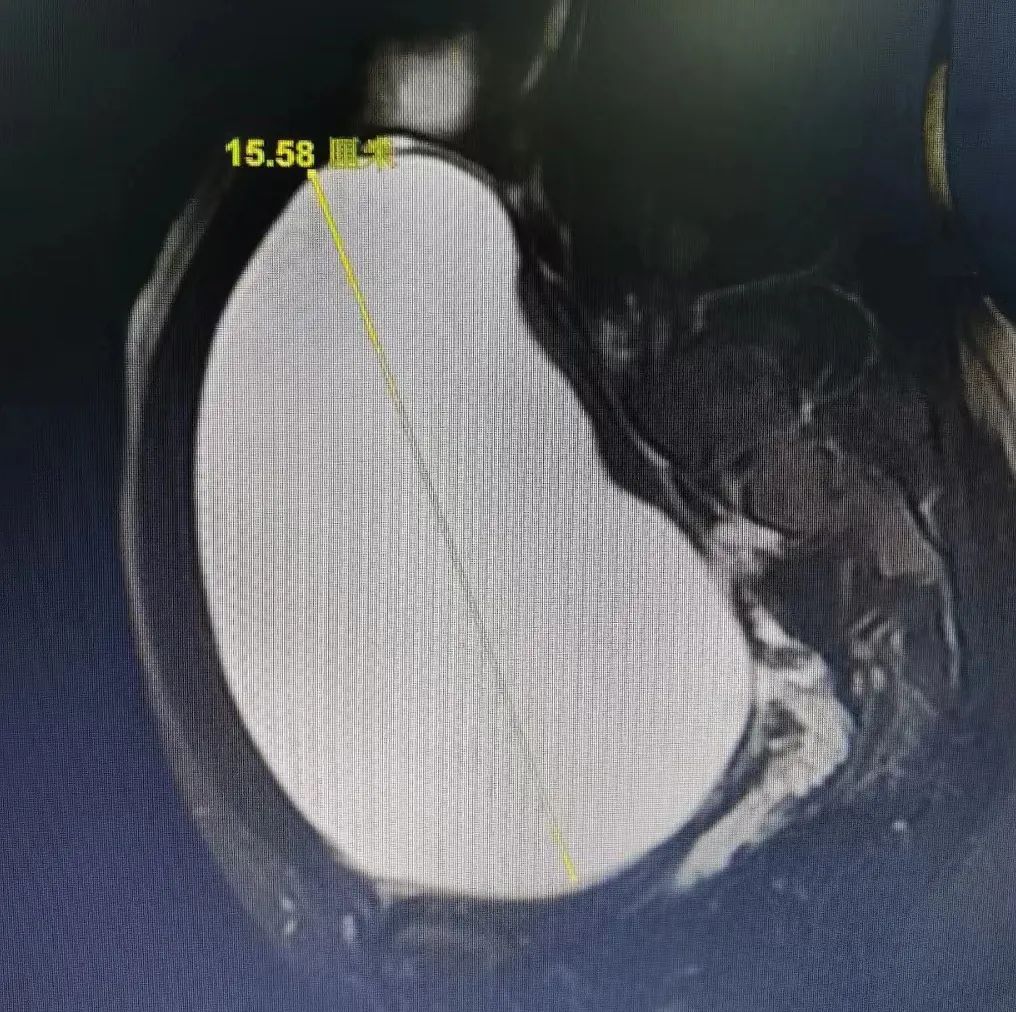

担心之下,家长带小清去B超检查,检查结果吓了一跳:小清腹部有个肿块,最大处直径近16厘米。随后磁共振检查清楚。肿块位于右侧卵巢,比排球略小一点。

医生根据经验判断,大概率是畸胎瘤,个头和怀孕5个月的子宫差不多大。